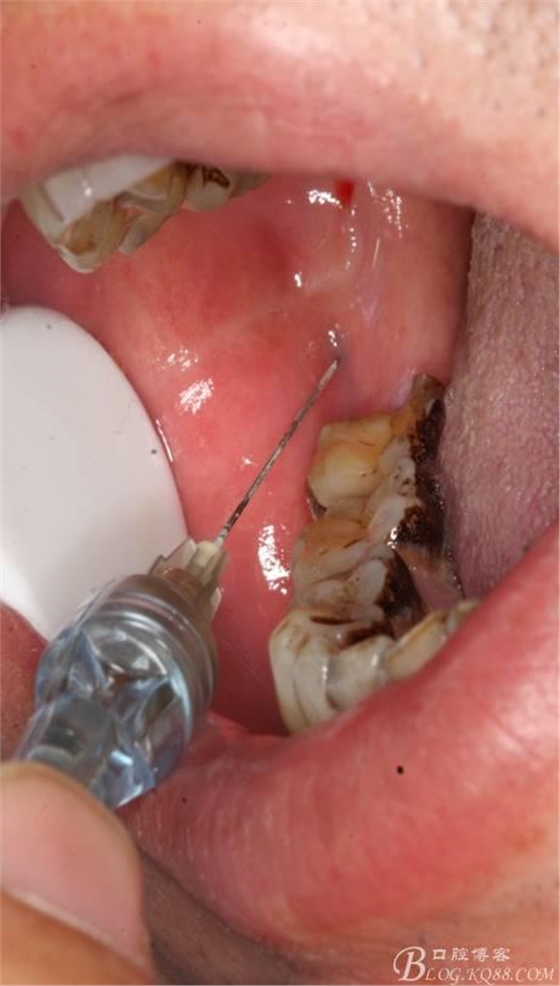

1.麻醉

2.切開(kāi)翻瓣